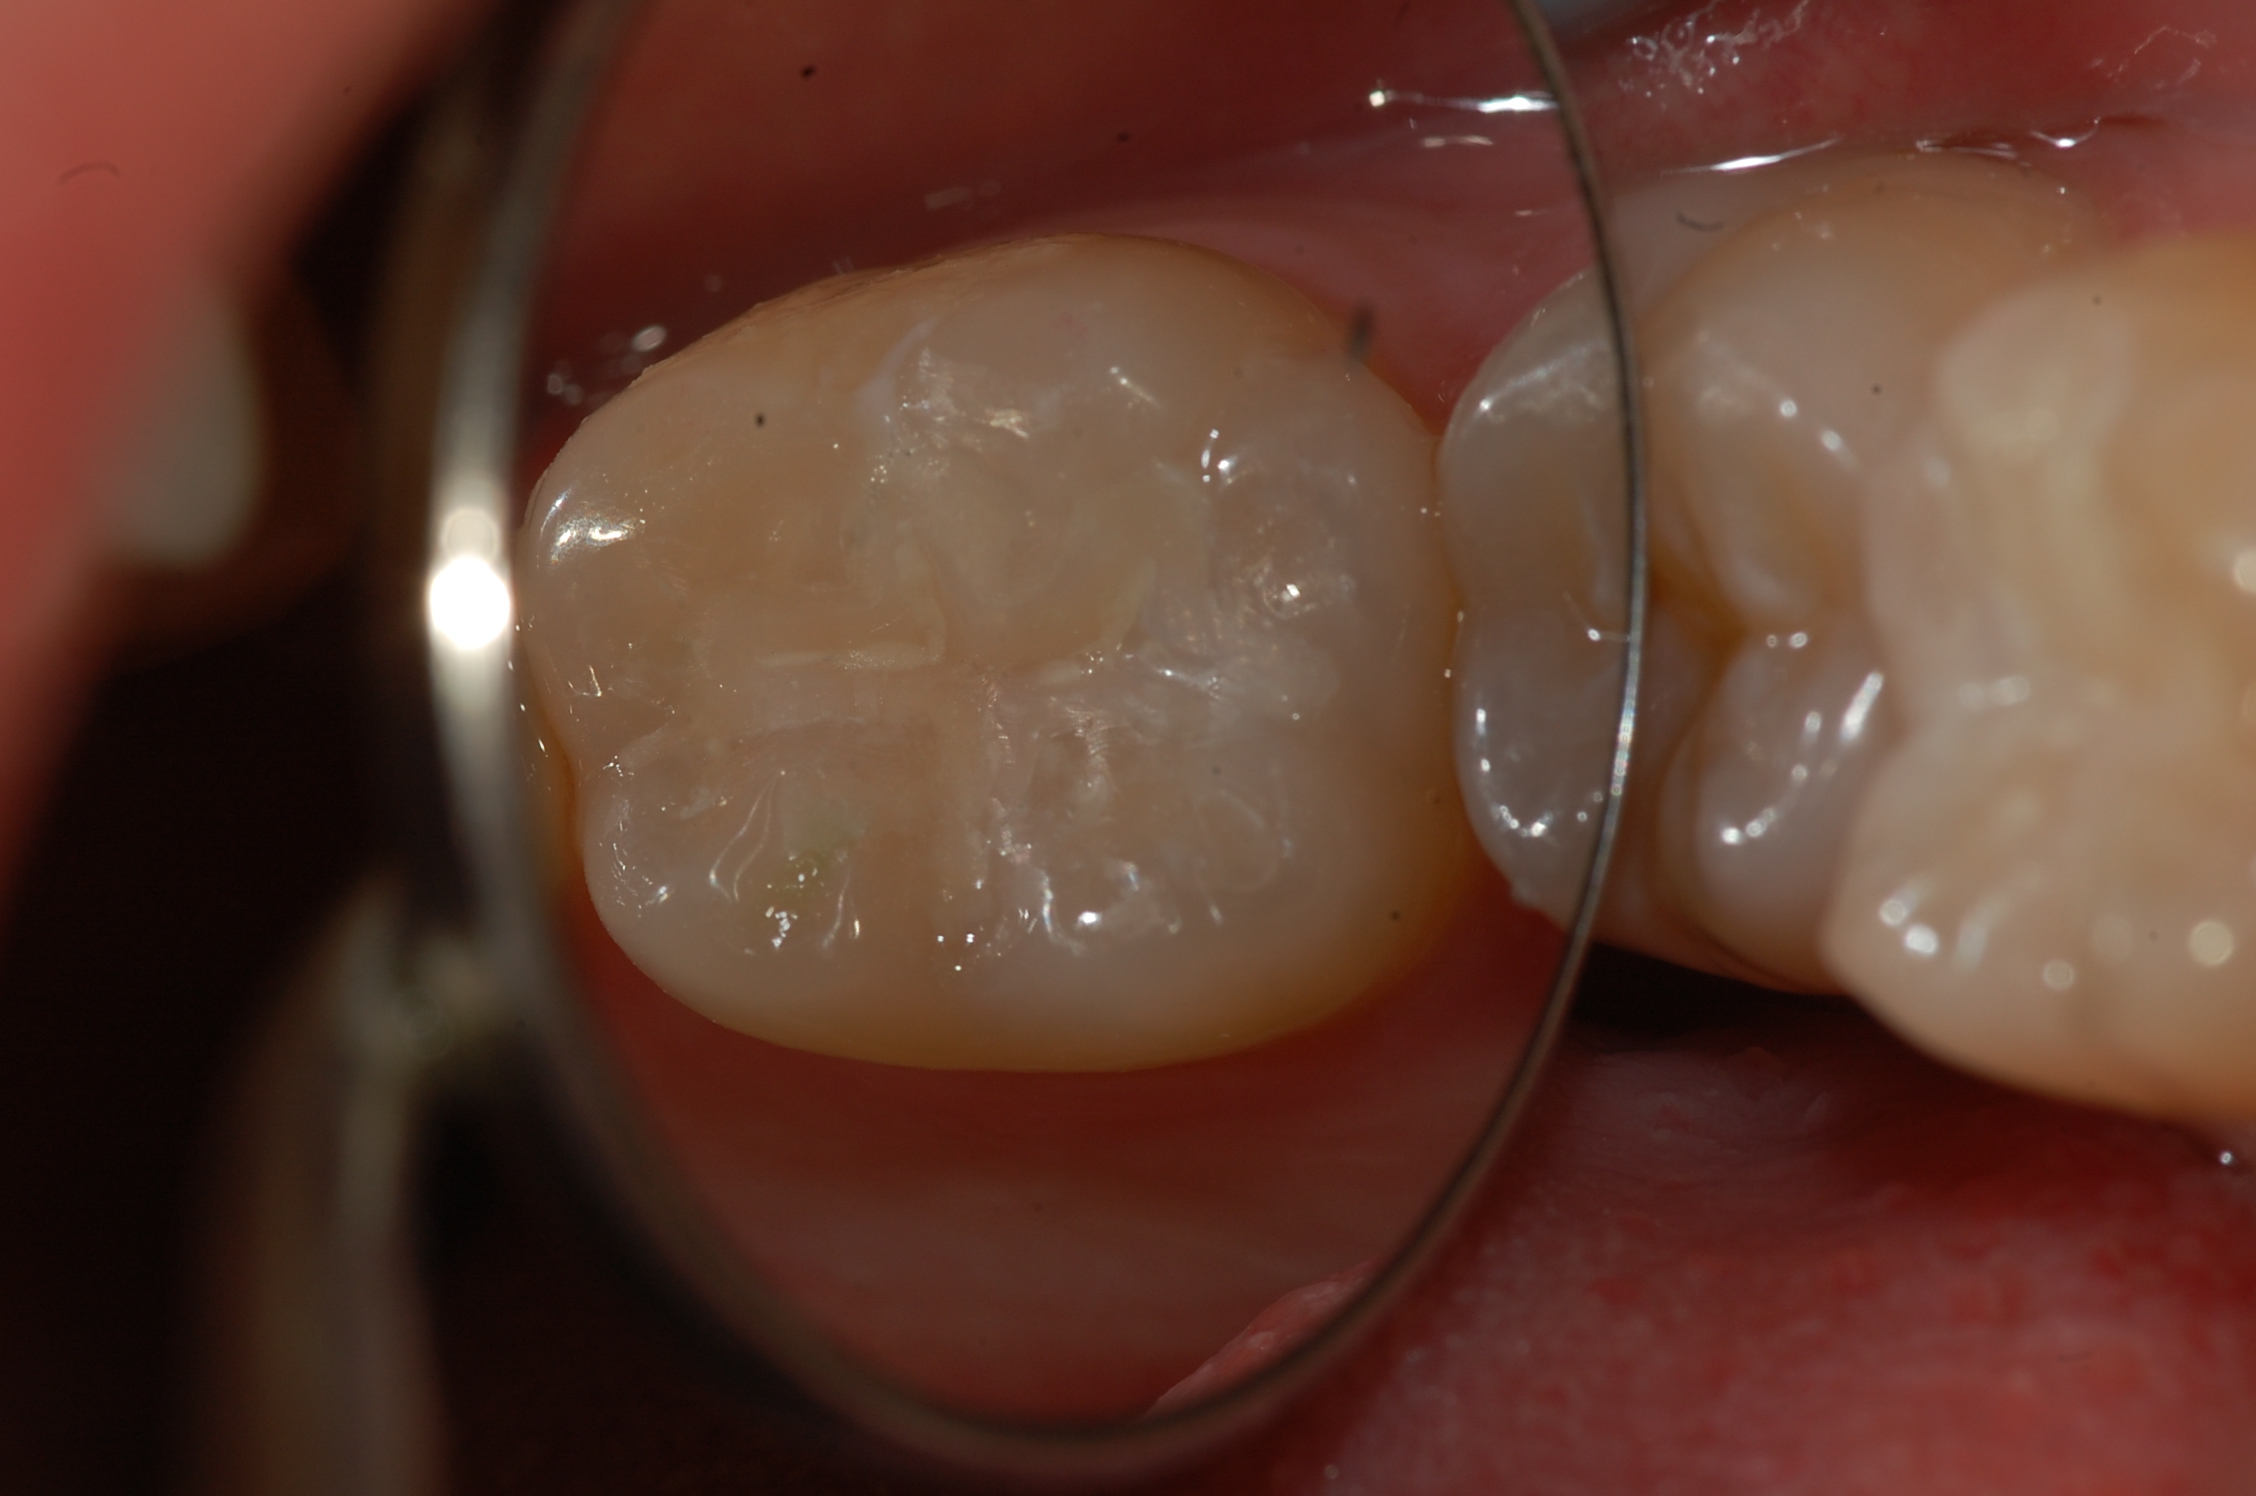

[보철,충치치료] 제목 : 하악구치

레진인레이